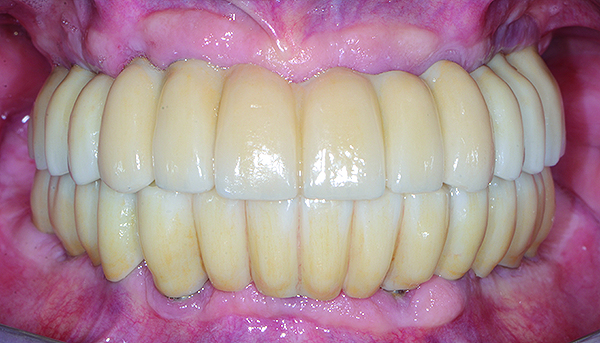

The maxillary prototype was adjusted, polished, and left to function with the mandibular provisional. The definitive maxillary zirconia restoration was then completed from the information provided by the prototype, and the cutbacks for the facial porcelain (Nos. 6 through 11) were done after milling but before sintering. Subsequently, the mandibular prototype was adjusted to the sintered and colored maxillary zirconia framework before the application of porcelain to Nos. 6 through 11 and final glazing (Figure 11). Following this step, the mandibular definitive monolithic zirconia restoration was milled, colored, and sintered. The facial porcelain (Nos. 6 through 11) was applied, and then both maxillary and mandibular restorations were stained and glazed (Figure 12). Both bridges were inserted at the same time (Figure 13 through Figure 15). Minor occlusal adjustments and oral hygiene access was verified and the zirconia surfaces polished. The bridge screws were torqued to 20 Ncm according to the manufacturer’s recommendation, and No. 24 was luted with a provisional cement. Postoperative radiographs were taken (Figure 16).

Fig 15. Intraoral frontal view of completed maxillary and mandibular zirconia restorations.

Figure 15

Fig 17. Intraoral frontal view of maxillary and mandibular zirconia restorations at 1.5 years.

Figure 17